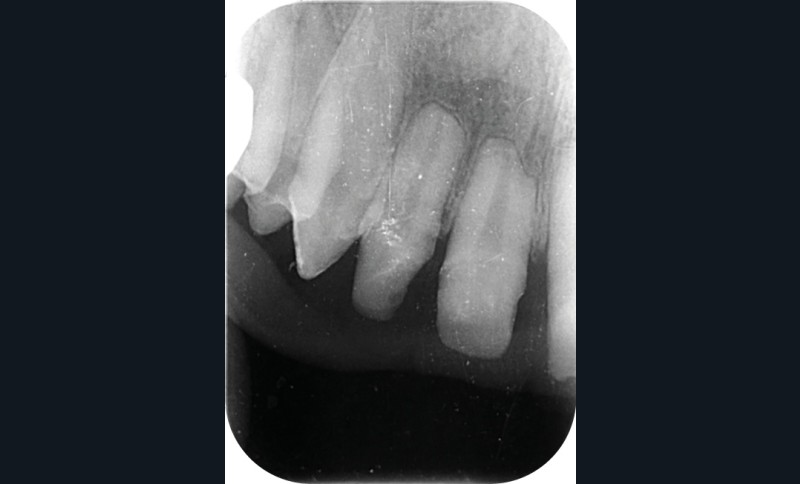

Une patiente âgée de 12 ans a été adressée au cabinet pour « une prise en charge complète sur le long terme » par son praticien traitant. Elle était accompagnée par sa mère. Elle présentait des couronnes transitoires en résine sur le secteur incisivo-canin au maxillaire ainsi que les premières prémolaires, des coiffes pédodontiques métalliques sur les premières molaires, une absence totale d’émail sur l’ensemble de la denture, à l’exclusion des bords libres des incisives mandibulaires (fig. 1 à 3). Le bloc incisivo-canin mandibulaire avait bénéficié de traitements radiculaires (fig. 4). Les incisives maxillaires présentaient des rhizalyses d’une importance significative (fig. 5 et 6). La patiente se plaignait d’hypersensibilités à la mastication et au brossage, la demande esthétique était forte.